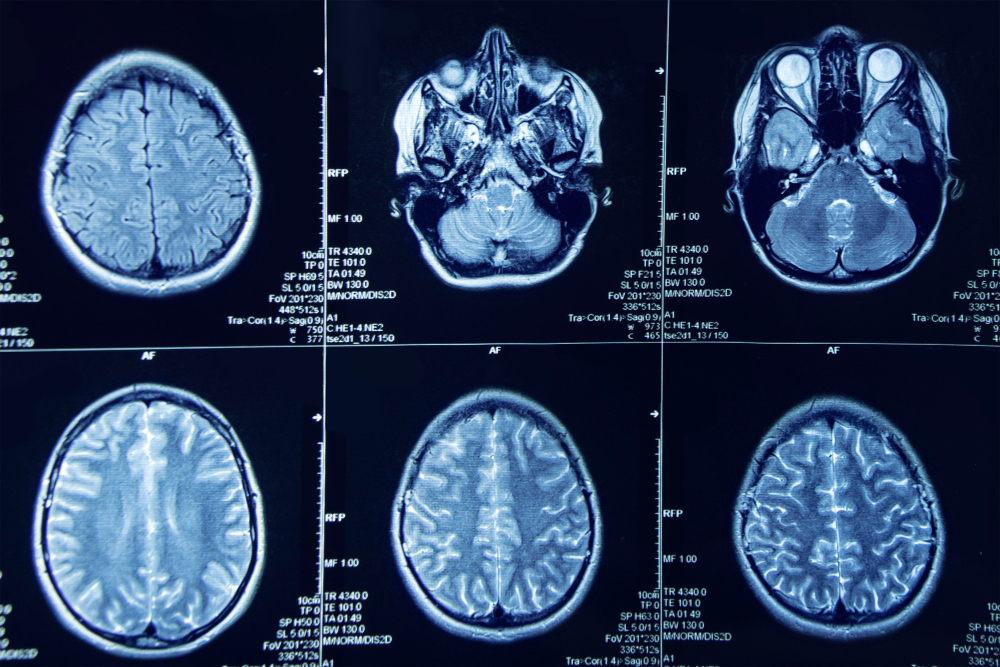

What is a CT Brain Scan? A CT Brain scan is a special type of X-ray. It takes detailed pictures of your brain. Doctors use